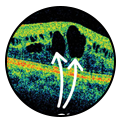

Diabetic Retinopathy Management

Such as photocoagulation or panretinal photocoagulation, halts blood and fluid leakage and shrinks abnormal vessels in the eye.

What does the green laser do in the eye?

A green laser, also known as a LION, is used to treat glaucoma and retinal diseases by targeting ocular tissue. A green laser can also be used to treat diabetic retinopathy by scarring the retina to prevent new blood vessels from forming.